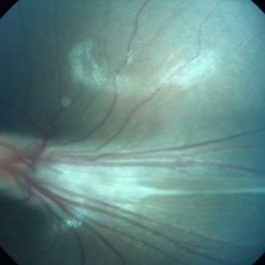

Familial Exudative Vitreoretinopathy

Fundus photograph of 25-year-old female with Familial Exudative Vitreoretinopathy ; right eye showing total retinal detachment with proliferative vitreoretinopathy.

Photographer: miss Ashwini borde

Imaging device: Carl Zeiss 450 plus IR

Condition/keywords: familial exudative vitreoretinopathy (FEVR)